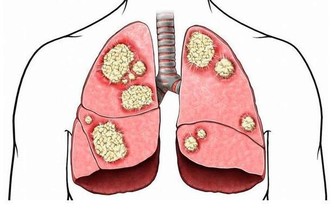

2.會致腦部供血不足: 可引起人體乏力、失眠、記憶力減退,並增大患老年癡呆症的可能。 3.會使心髒機能衰退: 引起心肌萎縮、動脈硬化、高血壓、冠心病等心血管疾病。 研究表明,坐著工作的腦力勞動者,冠心病發病率為12%,而體力勞動者僅為3%。 4.易患癌症: 久坐不動導致免疫細胞功能低下,對外界致病因數抵抗力下降,因此易得癌症。研究發現,久坐的人患結腸癌的風險明顯高於經常運動的人。 5.會造成消化功能減退: 易引起腸胃蠕動減慢,消化腺分泌消化液減少,出現食慾不振、腹脹、便秘等症狀。 6.會使男性提前進入更年期: 久坐不動的男性因缺乏鍛鍊,容易出現腹型肥胖;久坐不動,還會產生心理壓抑、無精打采、倦怠無力。總是「黏」在椅子上的男性腦力勞動者會比其他男性更早步入更年期。

12.女性久坐更易得3種癌: 研究發現,久坐對女性的傷害遠高於男性,它容易導致女性患癌,特別是乳腺癌、卵巢癌、多發性骨髓瘤的風險上升。 因此,請不要久坐!要經常起來活動活動。凡因工作需要久坐的人,每隔兩小時,應進行一次約10分鐘的活動,或自由走動,或做簡單運動操等。平時,也應多晨跑、散步、做健美操等,以避免疾病發生。